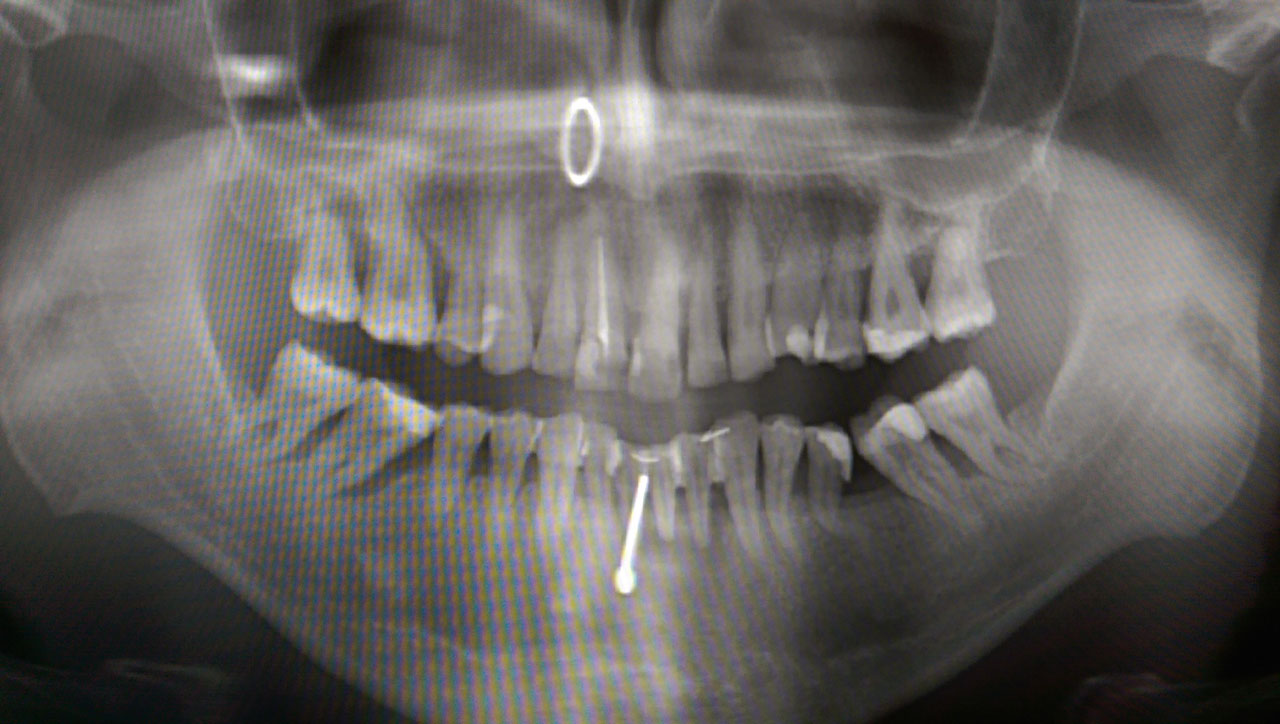

Alsó állcsont teljes rehabilitációja 72 óra alatt

Alsó állcsont teljes rehabilitációja 72 óra alatt, azonnal terhelhető implantátumokkal súlyos paradontitisben szenvedő dohányzó páciens esetében. Az alsó állcsont fogai mind mozogtak az előrehaladott fogágypusztulás miatt.

A fogakat eltávolítottuk, a gyulladt, fertőzött csontot kitakarítottuk, kifertőtlenítettük, majd azonnal implantáltunk.

Svájci, IHDE márkájú, azonnal terhelhető implantátumokat helyzetünk be, és ezekre harmadnapra rögzített, hosszútávú, fémvázas, esztétikus műanyaggal leplezett hidat ragasztottunk be.

Ezt az ideiglenes hidat a sebek gyógyulása miatt használjuk, de tartóssága miatt véglegesként is használható.

A legtöbb esetben, ahogy itt is, 6 hónap múlva porcelán hídra cseréljük, a teljes gyógyulás után.